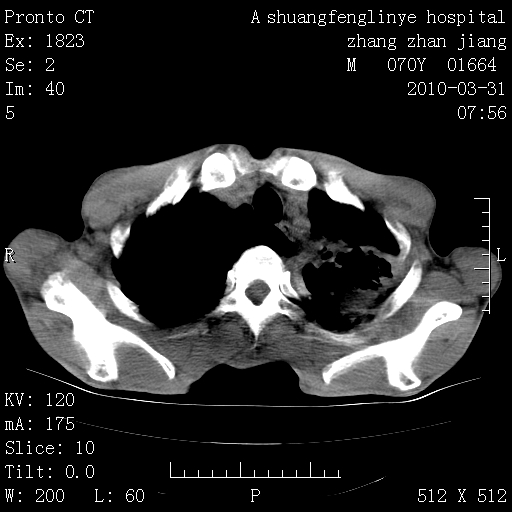

双上肺继发型tb并左上空洞形成,主动脉冠脉钙化。

1)两肺上叶继发性肺结核并左肺上叶空洞形成。2)冠状动脉及主动脉钙化。